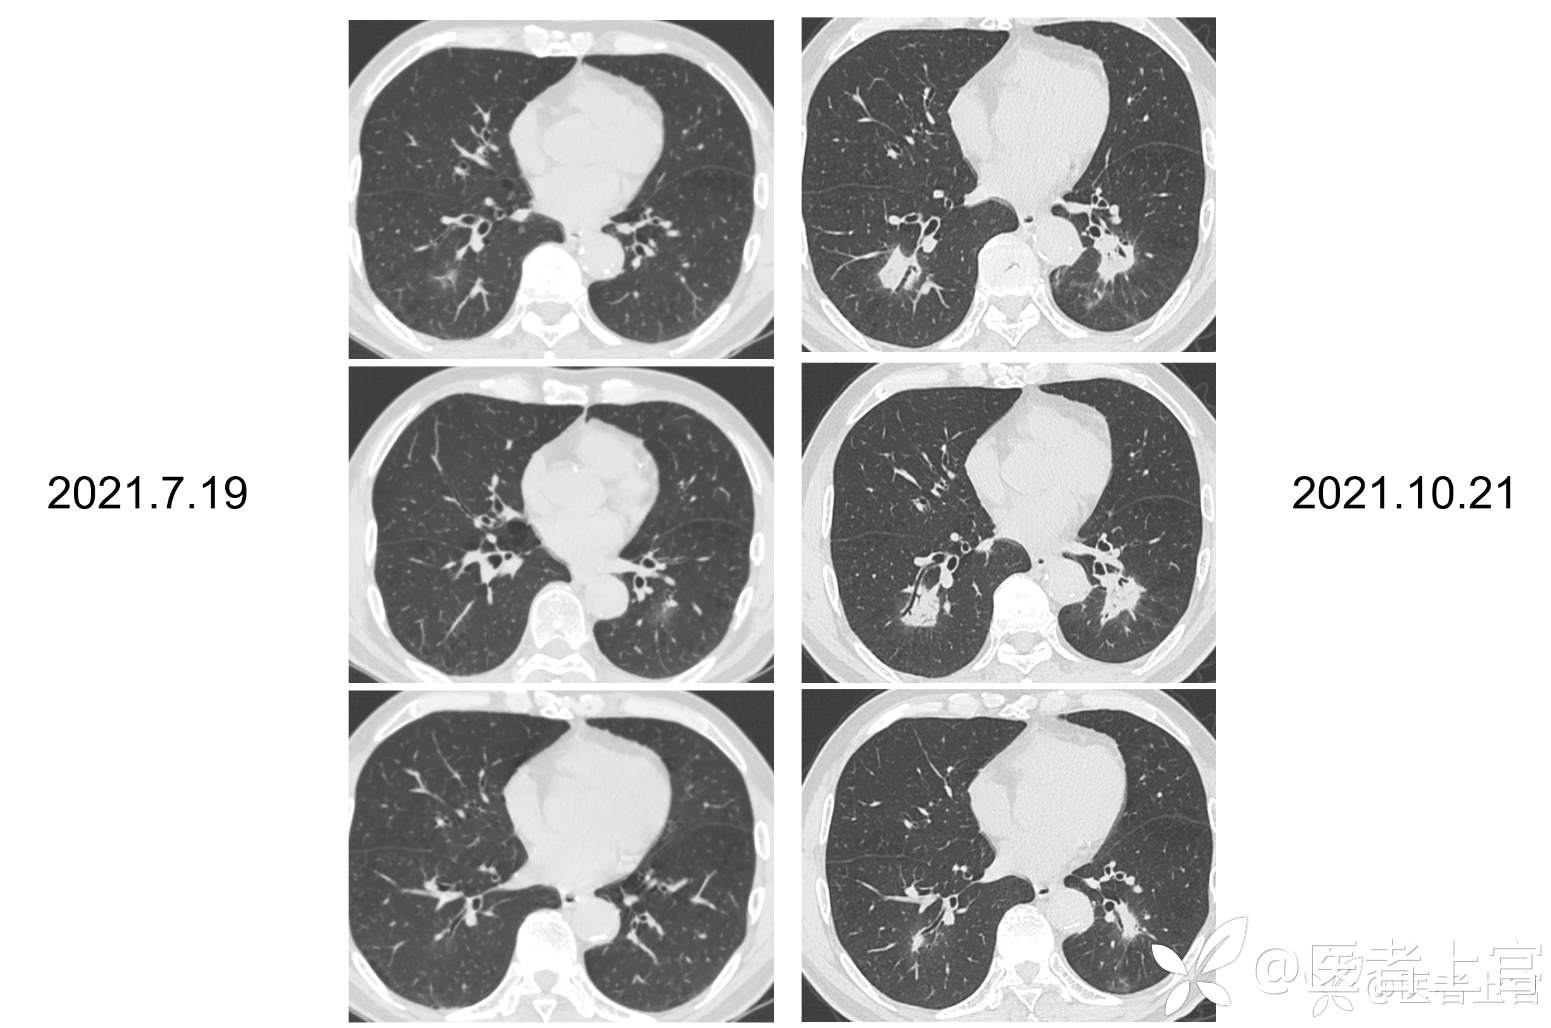

【7.19肺CT】两下肺斑片模糊影,渗出可能,建议抗炎后复查。两肺局限性肺气肿;左肺上叶及右肺下叶背段纤维、结节状钙化灶伴右肺下叶局部支气管牵拉扩张

【10.21肺CT】两下肺模糊实变灶,较前片(2021-7-19)进展,首先考虑炎症,建议抗炎治疗后短期复查。两肺局限性肺气肿;左肺上叶及右肺下叶背段纤维、结节状钙化灶伴右肺下叶局部支气管牵拉扩张。主动脉、冠脉硬化。

【7.19肺CT】两下肺斑片模糊影,渗出可能,建议抗炎后复查。两肺局限性肺气肿;左肺上叶及右肺下叶背段纤维、结节状钙化灶伴右肺下叶局部支气管牵拉扩张。主动脉、冠脉硬

【11-03胸部平扫增强】 两下肺团片实变影伴内部充气支气管征,目前倾向首先考虑炎症,两肺局限性肺气肿;左肺上叶及右肺下叶背段纤维、结节状钙化灶伴右肺下叶局部支气管牵拉扩张;主动脉、冠脉硬化。